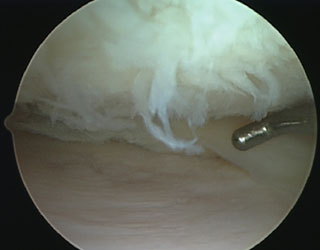

This Arthroscopic Knee Surgery procedure includes removal of loose chondral flaps and smoothing of the Articular Cartilage (chondroplasty). It is utilized for small areas of superficial cartilage damage in patients that experience joint pain and have associated mechanical symptoms. The goal of Arthroscopic Articular Cartilage Surgery is to eliminate catching and locking from these loose pieces of cartilage and to try to prevent propagation of these chondral flaps. The scraping action causes a healing response in the bone. In time new blood vessels enter the area and fill it with scar tissue (Fibrocartilage) that is like Articular Cartilage.

Arthroscopic Microfracture:

< 2 cm) of cartilage damage that are surrounded by healthy tissue. There is presence of rich blood supply in the bone beneath the cartilage. Microfracture procedures try to access this osseous vascular supply in order to heal cartilage defects. In this procedure small holes are created in the bone at the base of a cartilage lesion. This allows cells from the bone marrow to fill in the defect and stimulate new cartilage growth. This new cartilage is a scar-type of cartilage called fibrocartilage. Wide spread cartilage treatments are a contraindication to this type of management.